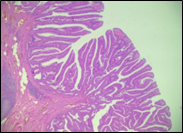

The present study concluded that, out of the total 77 patients with colorectal neoplasia, 17 (22.1%) had a high degree of differentiation (G1), 51 (66.2%) had a moderate degree of differentiation (G2), and 9 (11.7%) had a low degree of differentiation (G3). Figure 3 illustrates the different morphopathological forms of colorectal neoplasia observed in the patients included in the study.

A | B |

C | |

Fig. 3 Morphopathological forms of colorectal tumors (degree of differentiation) A – conventional highly differentiated colonic adenocarcinoma (G1) (HE stain, ×200) B – moderately differentiated (G2) conventional colonic adenocarcinoma (HE stain, ×200) C – conventional poorly differentiated colonic adenocarcinoma (G3) (HE stain, ×200) | |